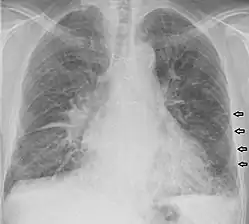

Ligne de Kerley

Les lignes de Kerley sont un signe de syndrome interstitiel sur une radiographie du thorax. Elles traduisent l'épaississement des septa interlobulaires dû à un infiltrat du tissu conjonctif (interstitium pulmonaire). On distingue les lignes de Kerley de type A (apical), B (basal), C (apical+basal) et D[1].